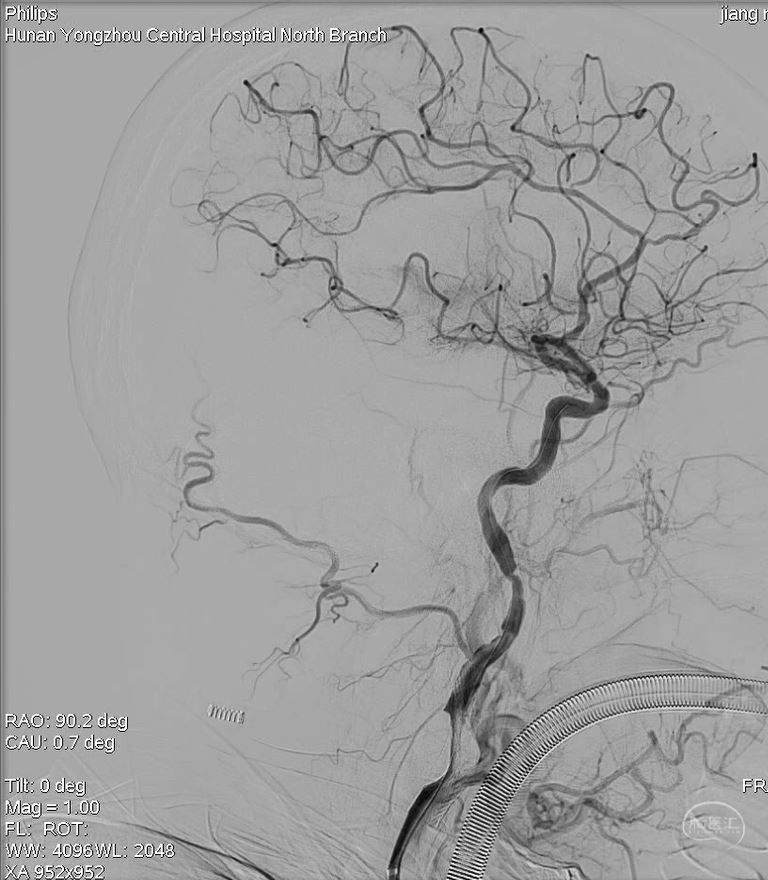

主动脉弓造影提示右侧颈内动脉闭塞。

右侧考虑颈内动脉C1段重度狭窄合并急性闭塞,眼动脉反流显影部分血管,右侧M1分叉部急性闭塞,右侧大脑前血流考虑血流灌注不足影响,且合并A2狭窄。

最后正侧位造影、通路造影、Dyna-CT。手术完成。

侧位造影

正位造影